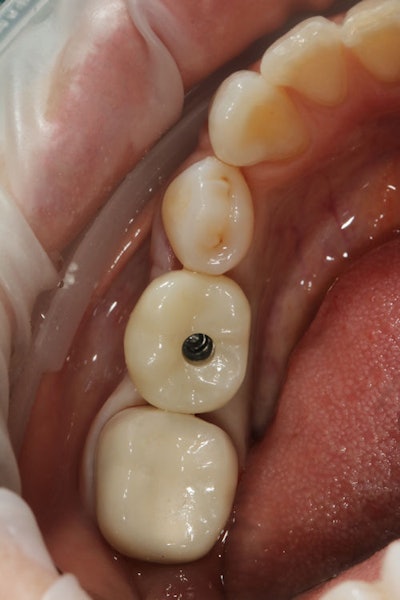

The hybrid crown was then tried in to verify occlusion and proximal contacts. (Figure 12). Once confirmed, the screw-access channel was sealed using Clearfil Majesty ES-2 composite to maintain aesthetics and function (Figure 13).

Figure 12: The screw-access channel with crown attached.

Figure 13: The screw-access channel was sealed using Clearfil Majesty ES-2 composite to maintain aesthetics and function.